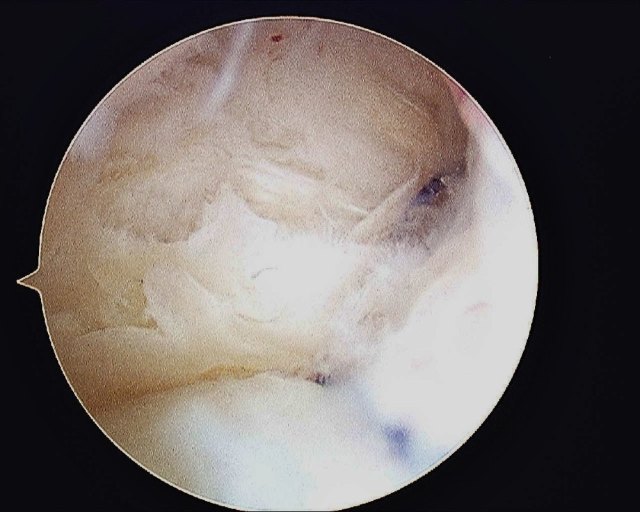

- The tear is repaired with an outside in technique with PDS 3/0 suture. The Smith & Nephew’s TFCC Mender device is used to pass the sutures through the torn TFCC. The sutures are tied outside the capsule while the ECU tendon is being protected by an assistant.

The 1st PDS suture that was passed through the TFCC is shuttled back into the joint and out of the capsule.